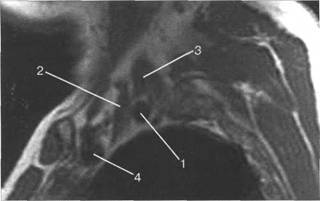

T2-BH(FATSAT).

I располагается позади. Иногда удается хорошо различить ин 10510f510k дивидуальное деление пучков. Ла-